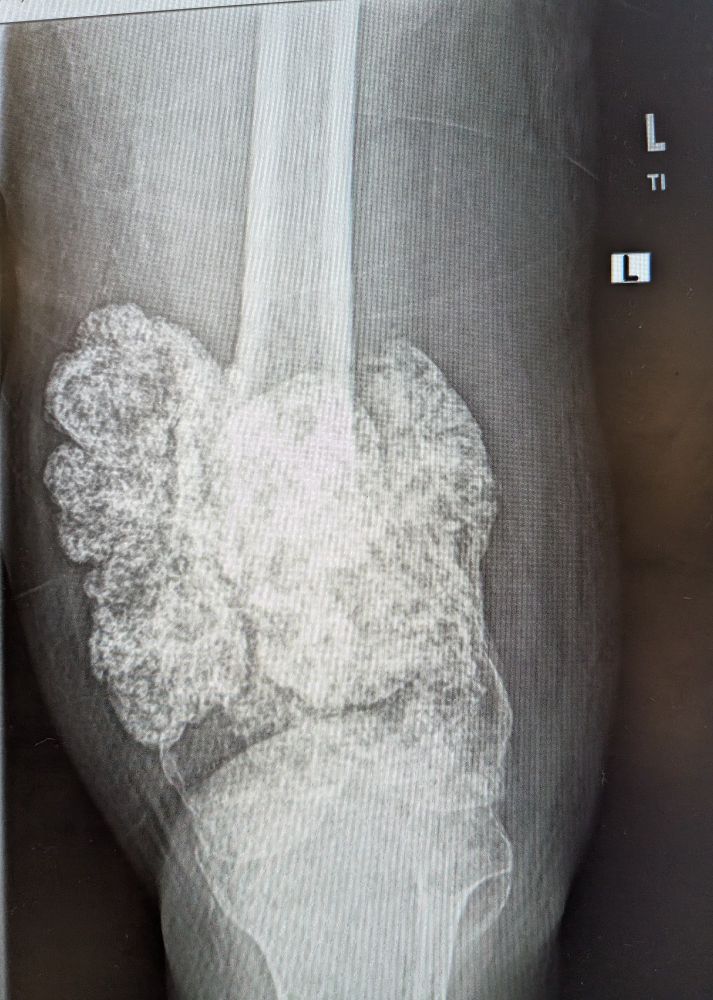

#ortho #onc #orthosky #oncsky #radsky #medaky #bones